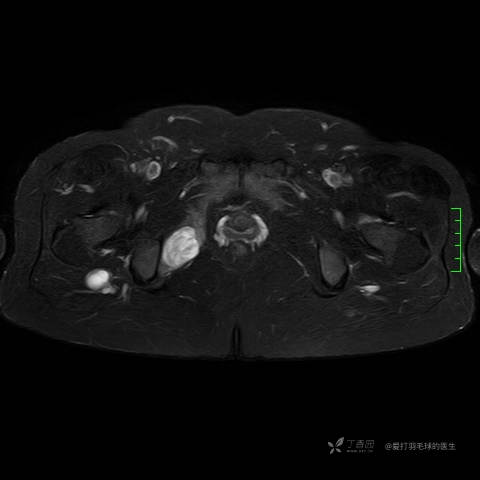

主诉:患者因反复右侧腰痛伴右下肢麻木2年余入院。

简要病史:自诉右甲状腺功能亢进症多年,规律服药,平素多有心悸、胸闷、活动后明显。既往腰椎椎管内肿瘤切除术。